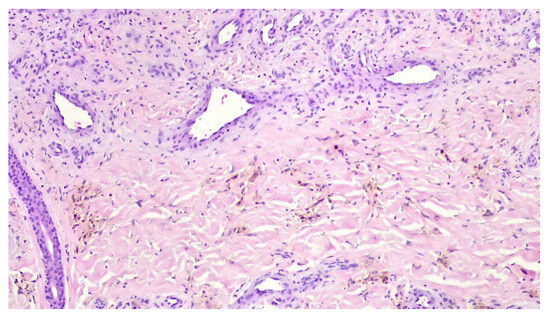

A punch biopsy was performed, and the histopathology disclosed moderate acanthosis, with focal spongiosis and small lymphocyte exocytosis. In the upper dermis, a marked neovascularization, composed of lobules of thick-walled capillaries, was observed in association with erythrocyte extravasation and hemosiderin deposition (Figure 3 and Figure 4). Immunochemistry for HHV-8 was negative (Figure 5). The clinicopathological correlation led to the diagnosis of AAD due to a venous malformation. This case illustrates a possible pathophysiological overlap with the venous malformation contributing to venous insufficiency.

Figure 4. Lobules of thick-walled capillaries and hemosiderin deposition.